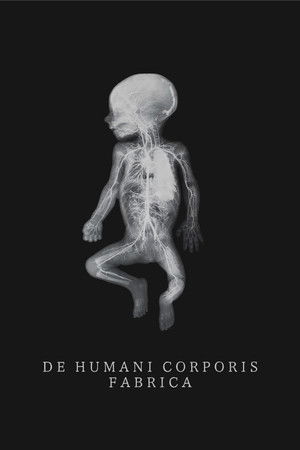

De humani corporis fabrica

(2023)Overview

An extraordinary adventure through the interior of the human body; or the discovery of an alien landscape of unprecedented beauty.